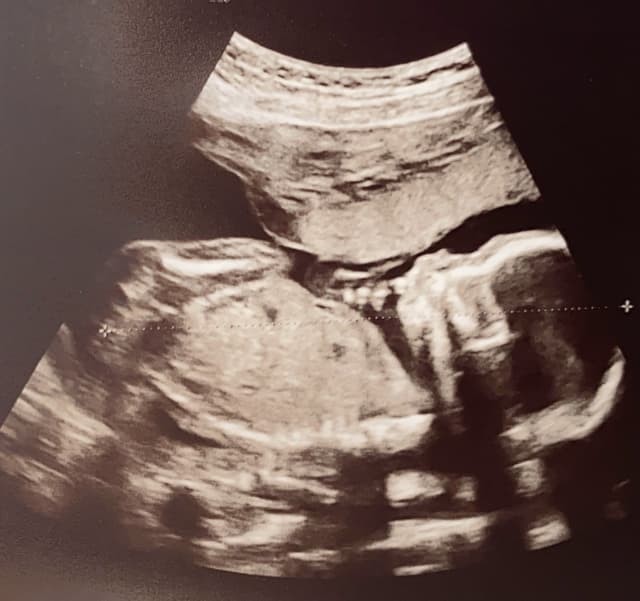

双子妊娠35週のお腹

いよいよ出産が近づく双子妊娠35週。

「おなかはどうなってる?」

私の双子妊娠35週の写真をご紹介。

赤ちゃんの体重は2000g以上を超え、2人合わせて4000g以上…‼︎

双子を妊娠しないと経験できないほどのお腹の膨らみになっていきます。

赤ちゃんの大きさは推定2400gと2200g。

ちなみに私はこの3日後、36週に入って出産しました。